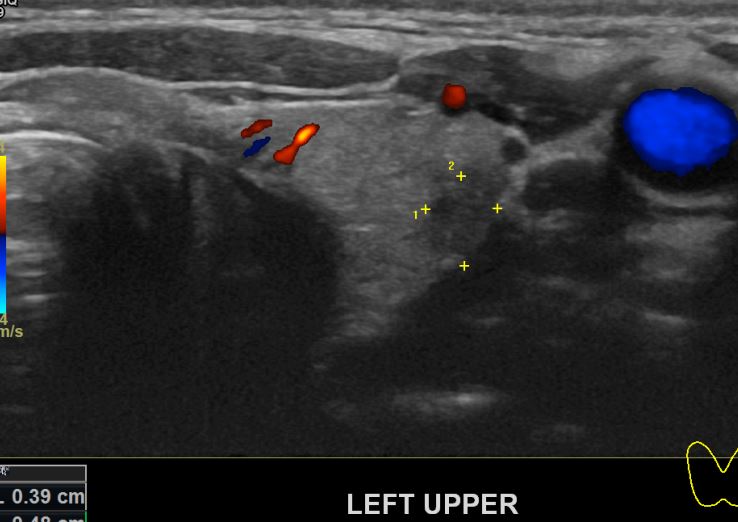

아산유외과 개원후 45번째 갑상선암 진단

상기환자 건강검진상 이상소견으로 내원하신 30대 여성분으로 의심스러운혹

세포검사진행후 갑상선암으로 진단되었읍니다